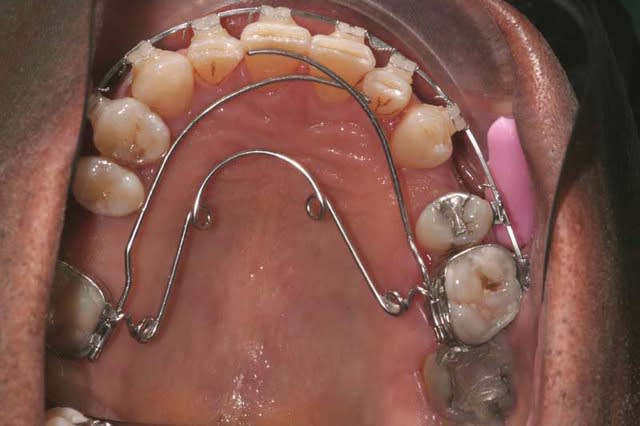

l’overjet se réduit (lentement)

Je rajoute un Q.H. Crozat

Et rallonge le bord libre des Inc. Sup.